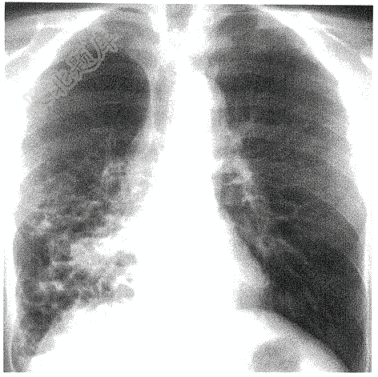

- 单项选择题老年男性患者,因反复咳嗽、咳脓痰20余年,加重1周入院。既往有肺炎病史。有长期吸烟史。胸片如下图,患者目前最有可能诊断是( )

A、支气管扩张

B、支气管肺炎

C、浸润性肺结核

D、肺不张

E、右肺下叶肺癌